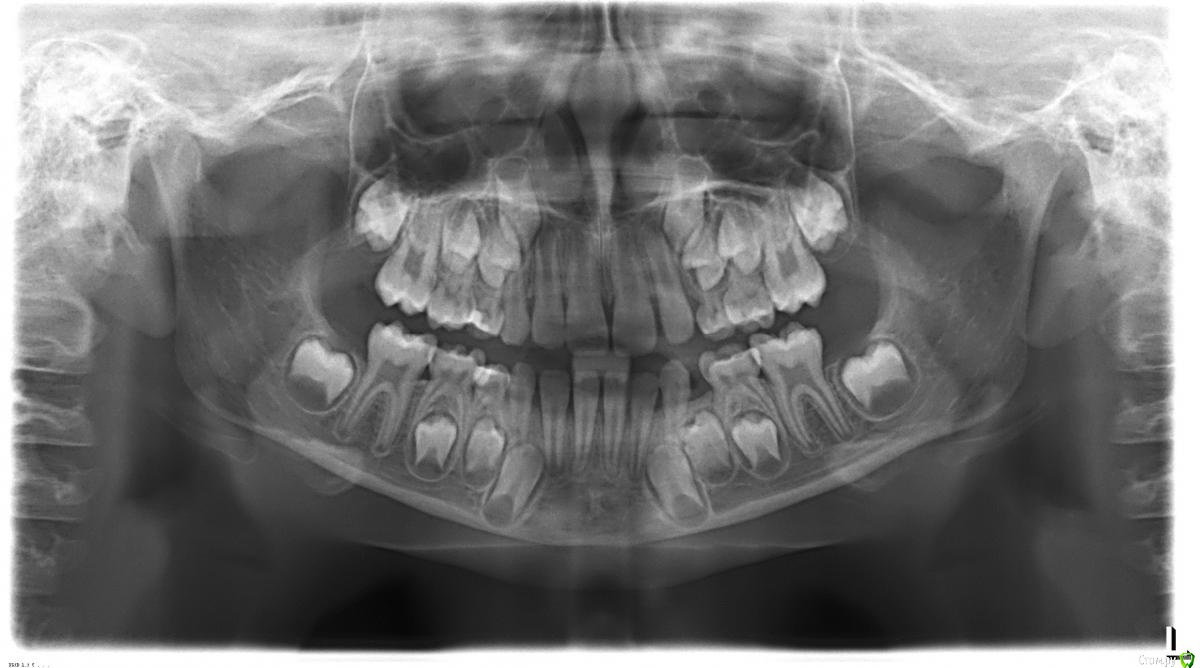

Светка255 Опубликовано 2 февраля, 2016 Поделиться Опубликовано 2 февраля, 2016 Здравствуйте, уважаемые врачи!Ребёнок, 8 лет, мезиальный прикус. Есть два различных мнения по поводу исправления:1). ночная капа OCCLUS-O-GUIDE.2). аппарат Брюкля.Мне сложно определиться, я не специалист, поэтому прошу ваших мнений и комментариев.Заранее спасибо! Ссылка на комментарий